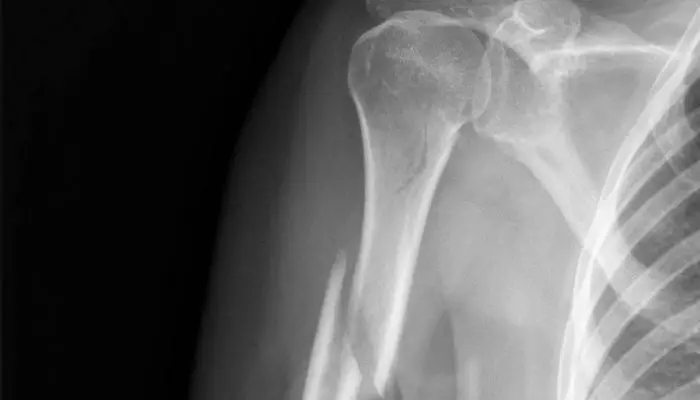

HUMERUS

The humerus is the bone of our upper arm, spanning from the shoulder to our elbow. As it attaches to our shoulder at the glenohumeral joint, the humerus, especially the proximal head, is the site of a lot of muscular attachments. It is movement of the humerus which allows us to lift and move our arm, and so it is integral to many of our daily tasks. Fracture of the humeral neck is what people usually call a broken shoulder and can severely limit our ability to complete day-to-day tasks.

Fracture of the humerus will usually occur via a fall onto an outstretched arm though less common causes include fall onto a bent elbow or the point of the shoulder, or even direct trauma to the upper arm such as in a motor vehicle accident. The fracture will present with acute pain, loss of function of the upper limb and swelling, bruising and inflammation.

WHAT IS THE TREATMENT OF A HUMERAL FRACTURE?

Shoulder Physiotherapy treatment will be incredibly important to guarantee a good recovery for a humeral fracture. As there is often multiple fractures, activation of muscles can cause deformation or abnormal healing of the bone. In addition, as there will be a significant period where the limb is immobilised, it will be important to consult a physiotherapist on a reloading program to make sure that muscular strength and size is regained, and that muscles activate properly to guarantee good movement.

Tightness or stiffness will also occur around the joint, therefore a shoulder physio will help to relieve pain and get full function back as soon as possible.